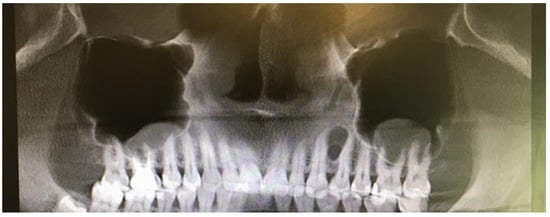

Figure 1. Panoramic radiograph slice from CBCT evaluation of LPC.

A 35-year-old female patient presented with a small, well-defined lesion on the attached gingival area, approximately 5/6 mm in diameter between roots of teeth 23–24, reported to the Privat Dental Clinic. The patient’s main concern was focused on gingival asymmetry and a tumor-like mass, painless and sometimes tender on tooth brushing. Clinical anamnesis revealed the occurrence of this asymptomatic mass for over 6 months. Because of swelling and atypical cortical expansion, the patient was referred for consultation and treatment. The patient was generally healthy without any chronic illness or important medical and dental past. A routine panoramic radiograph revealed a well-defined, radiolucent, left maxillary lesion located between the roots of the canine and first maxillary premolar (Figure 1 and Figure 2).